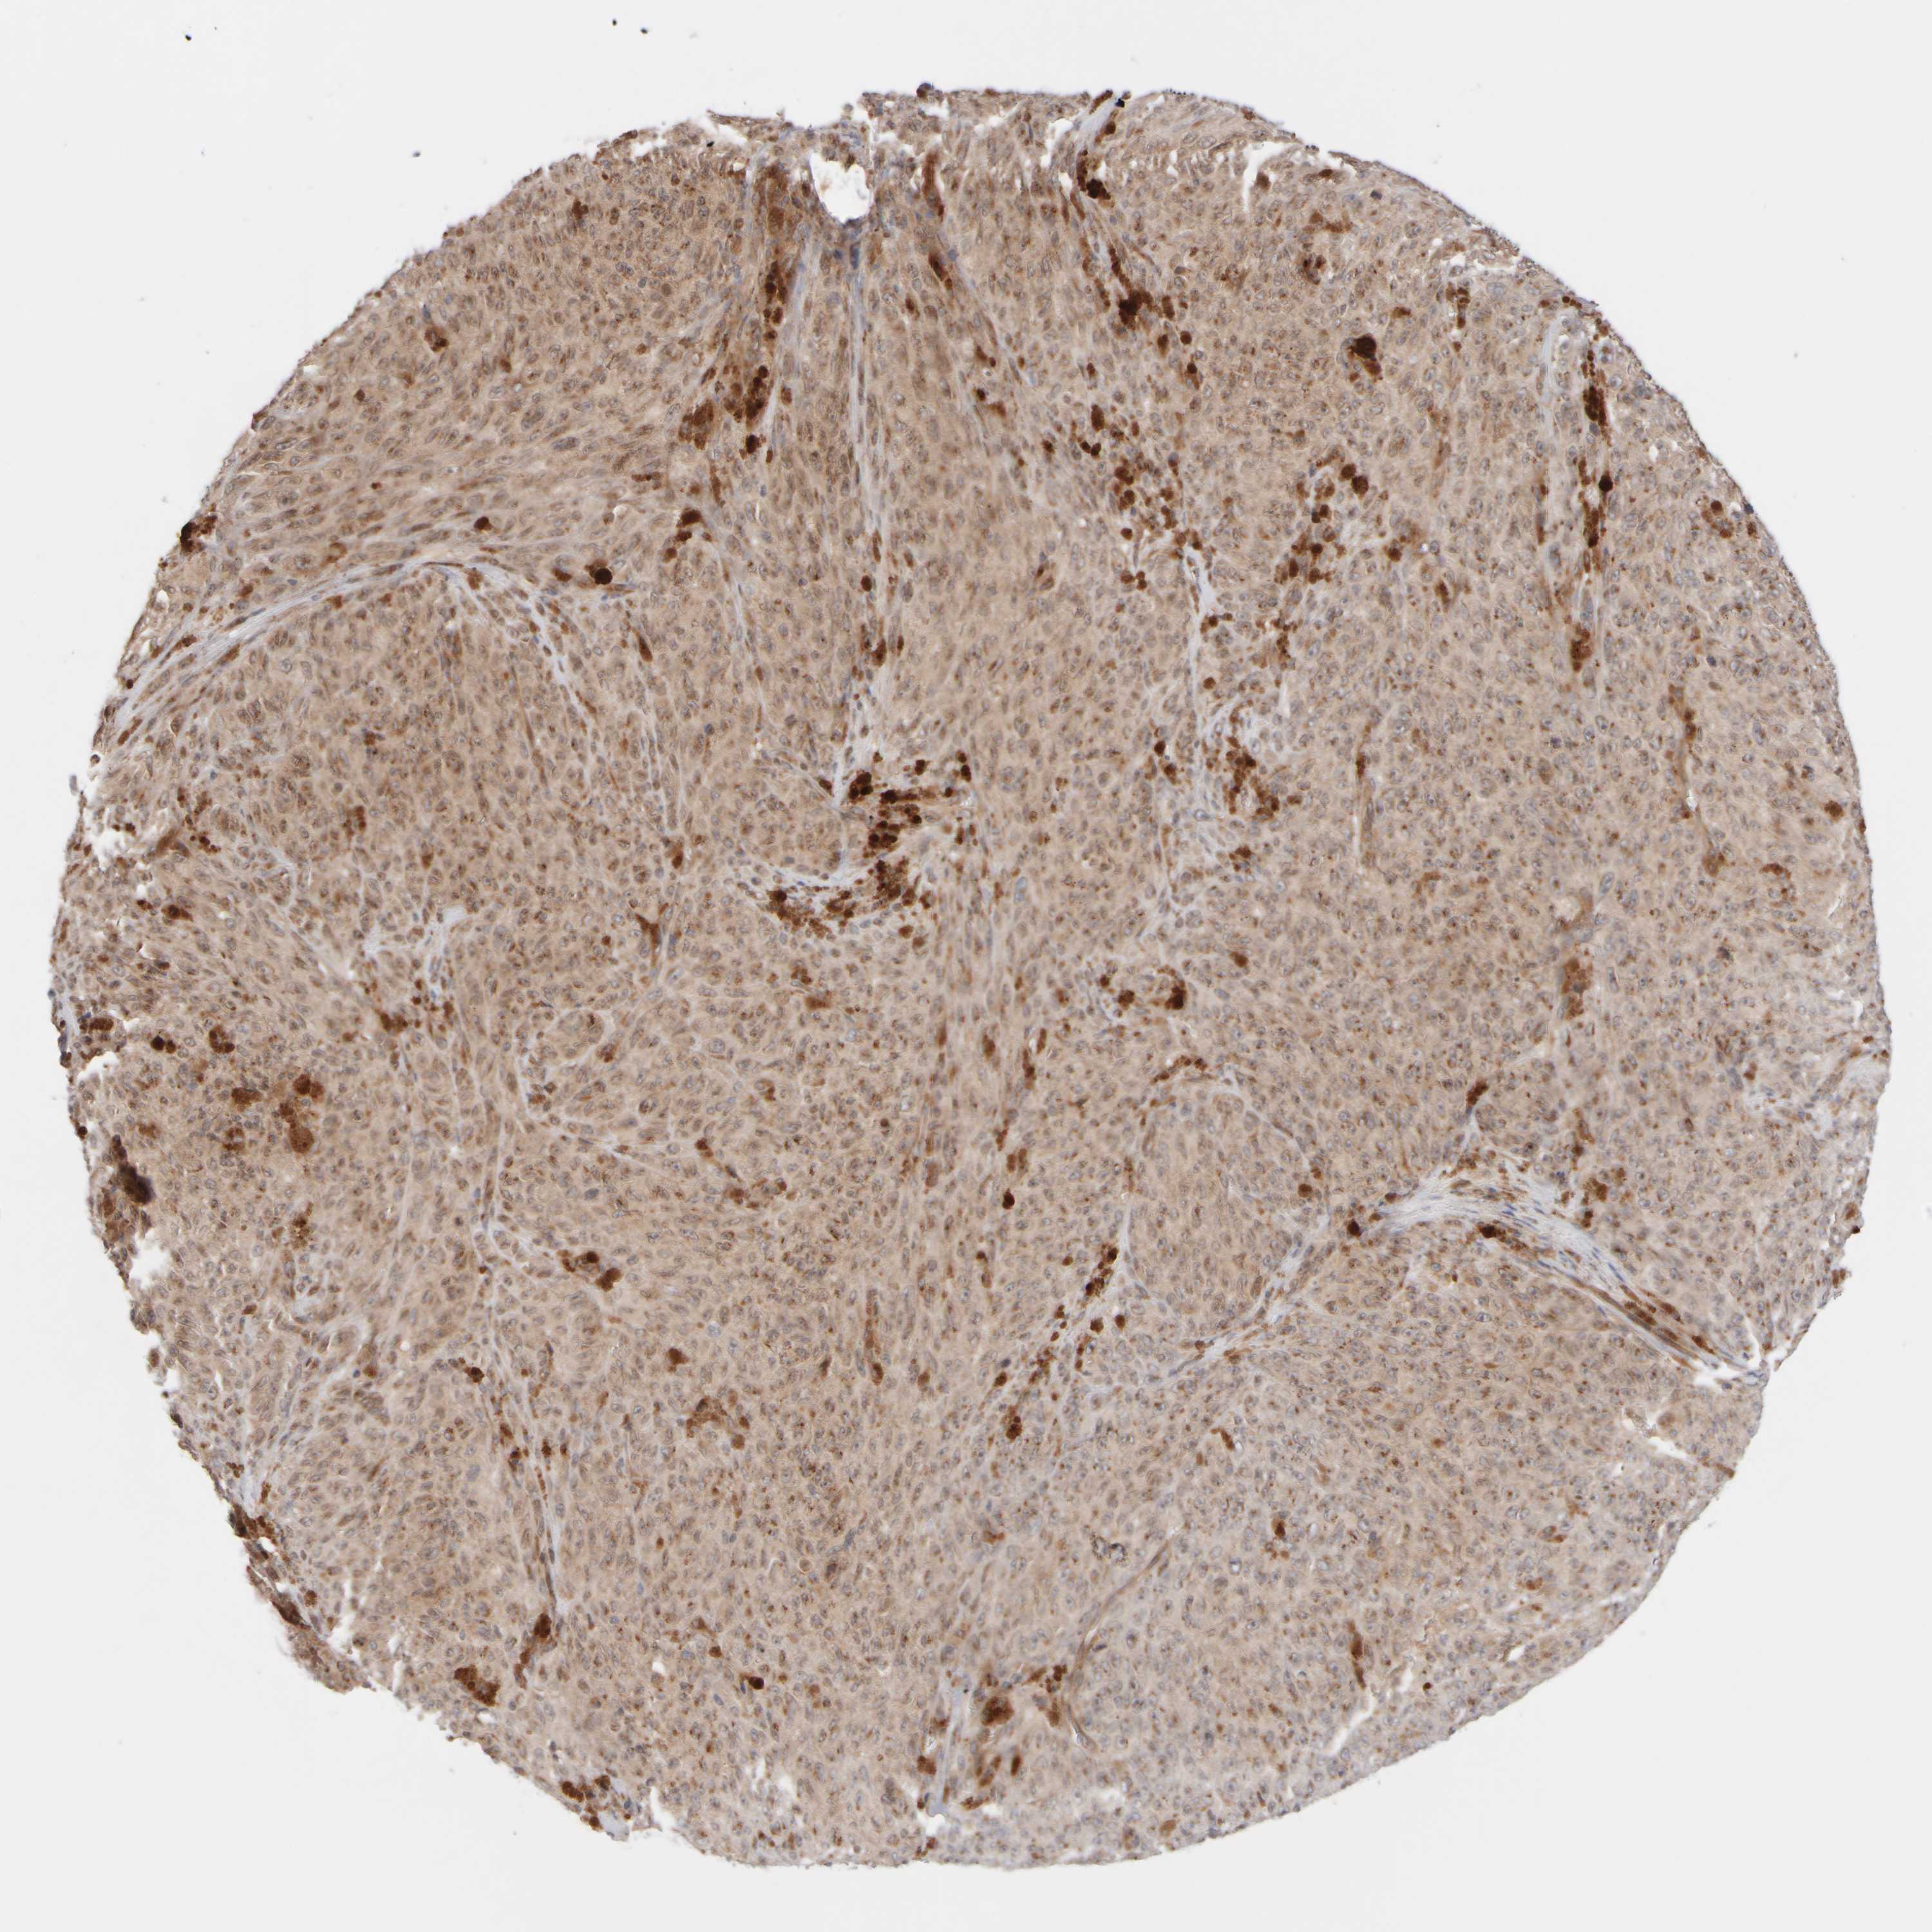

MELANOMA - Protein expressioni

A mouse-over function shows sample information and annotation data. Click on an image to view it in a full screen mode. Samples can be filtered based on level of antibody staining by selecting one or several of the following categories: high, medium, low and not detected. The assay and annotation is described here.

Note that samples used for immunohistochemistry by the Human Protein Atlas do not correspond to samples in the TCGA dataset.

Antibody stainingi

Antibody staining in the annotated cell types in the current human tissue is reported as not detected, low, medium, or high, based on conventional immunohistochemistry profiling in selected tissues. This score is based on the combination of the staining intensity and fraction of stained cells.

Each image is clickable and will lead to virtual microscopy that enables deeper exploration of all samples and also displays staining intensity scores, fraction scores and subcellular localization as well as patient and tissue information for each sample.

Antibody HPA018799

Antibody HPA019648

Antibody HPA024367

Staining

High

Medium

Low

Not detected

Intensity

Strong

Moderate

Weak

Negative

Quantity

>75%

75%-25%

<25%

None

Location

Nuclear

Cytoplasmic/membranous

Cytoplasmic/membranous,nuclear

Malignant melanoma, NOS

Malignant melanoma, Metastatic site